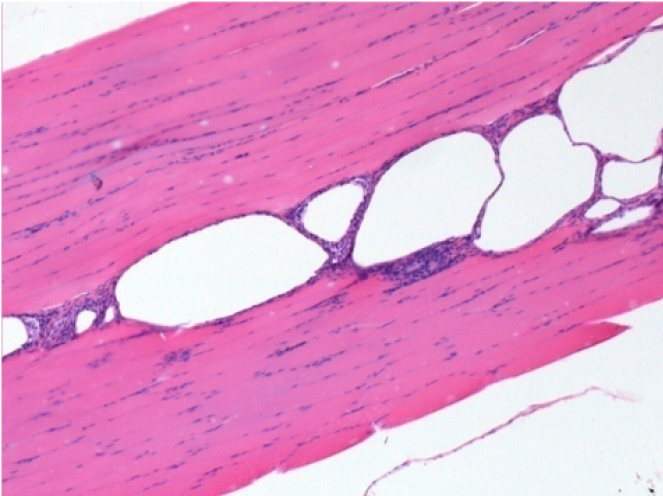

1 month after Endopeel Injection 0.1ml in the right pretibial muscle.

What is seen in black on the pictures is not a necrosis like could imagine some scientifics !

In fact, 4 conclusions have to be taken in consideration